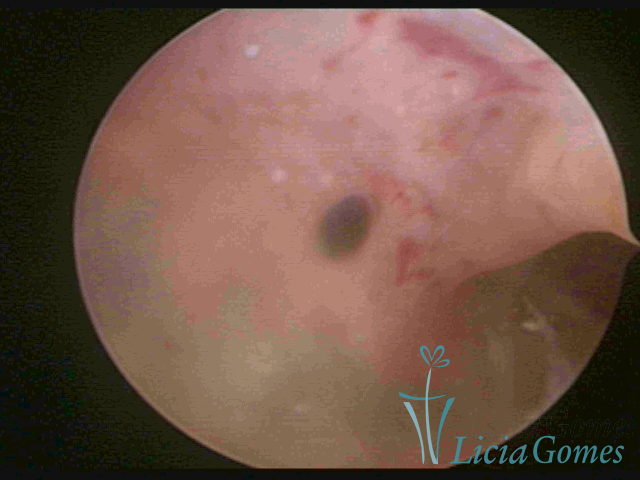

ADENOMYOSIS

The presence of endometrial tissue on the muscular layer of the uterus.

Video hysteroscopy allows diagnosing the lesions next to the superficial myometrial layers next to the endometrium, allowing the view of in situ, purplish, or chocolate brown lesions.